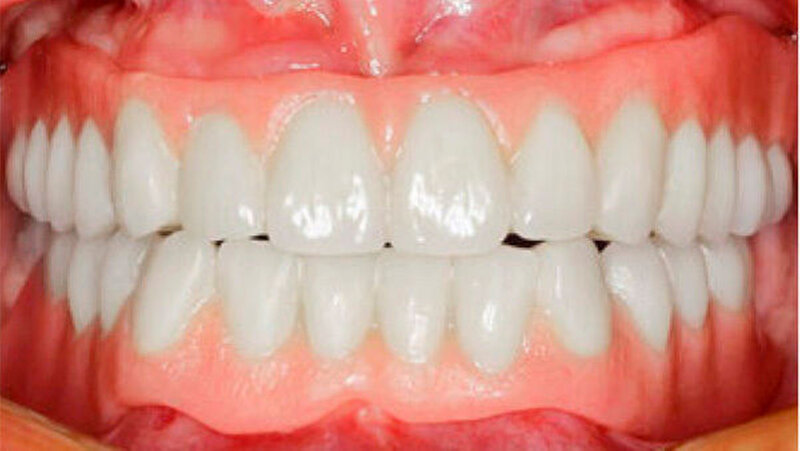

Durch Einbeziehung der Restbezahnung als Pfeilerzähne, und unter Beachtung deren Vitalerhaltung konnte der Patient funktionell und ästhetisch mit stabil verankerten Hybridprothesen rehabilitiert werden (Abb. 14 und 15). Teleskopkronen und -prothesen weisen Studien zufolge eine gute Langzeitprognose auf. Eine regelmäßige Nachsorge ist aber entscheidend für den Erfolg der Rekonstruktion. Da die Speichelmenge bei diesem Patienten im Normbereich liegt, ist diesbezüglich nicht von einem erhöhten Kariesrisiko auszugehen. Eine ungenügende Mundhygiene oder Mitarbeit hingegen stellen Risikofaktoren für biologische Komplikationen wie Parodontitis oder Karies dar. Nachteilig für den Erfolg der Rekonstruktion kann sich die relativ geringe Pfeilerzahl und deren Verteilung im Kiefer auswirken (Wöstmann et al. 2007).

Aufgrund des anatomisch sehr ungünstigen Prothesenlagers war der Erhalt der Restbezahnung im Oberkiefer anzustreben. Nach Kariesexkavation und Wurzelkanalbehandlung konnten beide Zähne mit einer Wurzelstiftkappe versorgt und die alten Prothesen entsprechend umgebaut werden. Im Anschluss an die Meisterabformungen und an die Ausrichtung der Wachswälle wurden die Modelle schädelbezogen einartikuliert, und die Prothesenzähne nach ästhetischen und funktionellen Richtlinien aufgestellt. Eine bilateral balancierte Okklusionsbeziehung konnte umgesetzt werden. Im Oberkiefer wurde eine gerüstverstärkte Totalprothese hergestellt, die auf den beiden Wurzelstiftkappen 16 und 26 verankert war. Im Unterkiefer konnte die Patientin mit einer Totalprothese versorgt werden (Abb. 21 bis 23).